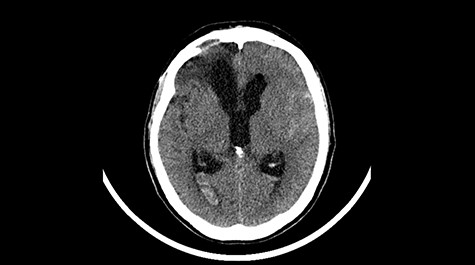

A 49-year-old patient presented after surgical treatment of nasal polyps, with headache and consciousness disorders (behavioral changes, drowsiness and allophenic orientation disorders). Computed tomography (CT) scan showed (Fig. 1) a presence of blood in fluid spaces, widening of the ventricular system (without active hydrocephalus features) and presence of air in the frontal horns of the lateral ventricles and features of cerebral edema. Due to the subarachnoid hemorrhage, an angio-CT and CT scan was performed, showing no vascular malformation. The patient's condition deteriorated with a drop in Glasgow Coma Scale (GCS) to 9, strongly expressed meningeal syndrome and a fever of > 38°C. In the performed cerebrospinal fluid examination a typical picture for bacterial infection, cultures negative. Treatment was implemented in accordance with the neuro-infections algorithm. Clinical and laboratory features of neuroinfections have withdrawn. The neurological condition of the patient improved to GCS 11. Control head CT (Fig. 2) showed enlargement of the ventricular system with cerebrospinal fluid transudation.

Head CT—state before VP shunt implantation. (Department of Neurosurgery own material).

After improvement of patient’s neurological status, a CT scan of the head revealed enlargement of the ventricular system with the features of cerebrospinal fluid transudation (Fig. 2), thus the patient has been qualified for a VP shunt implantation (Fig. 6).